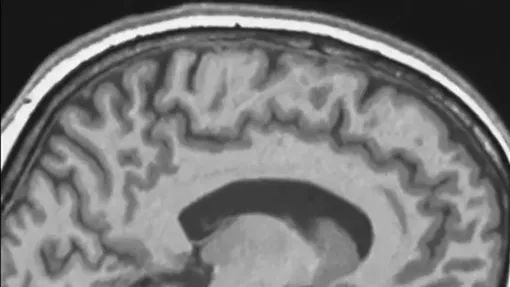

Длительное пребывание в космосе меняет не только мировоззрение человека, но и саму анатомию его головы. Исследование, опубликованное в журнале PNAS, показало, что под воздействием микрогравитации мозг систематически смещается назад и вверх, и слегка наклоняется. Чтобы зафиксировать этот эффект, исследователи разделили структуру мозга на 130 отдельных областей и изучили каждую из них.

Во время космического полета мозг человека смещается и поворачивается внутри черепа

У некоторых участников, находившихся на орбите долгое время, смещение тканей достигало 2,52 миллиметра. Такие изменения нельзя назвать локальными: они затрагивают обширные зоны мозга и напрямую связаны с тем, как долго человек находился в условиях низкой гравитации — от коротких двухнедельных полетов до годовых экспедиций.